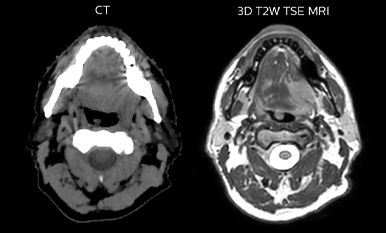

Epidermoid carcinoma of the left tongue base

The patient was diagnosed with an epidermoid carcinoma of the base of the left invading the amygdala lodge and the amygdaloglossal groove. Radiochemotherapy with curative aim was prescribed with a dose of 70 Gy for the tumor, 66 Gy on the suspicious nodes and 56 Gy on the elective drainage areas - in 33 fractions.

Comparison of CT simulation scan (left) and T2W 3D MRI (right)

MR-based target contouring on 3D T2W TSE in transversal, sagittal and coronal planes.